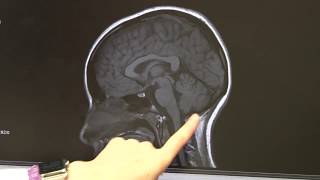

Studying children's brains to understand concussions video

Studying children's brains to understand concussions

Studying children's brains to understand concussions